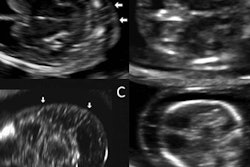

Fetal brain on an A-plane image before volume enhancement (left) and after adaptive volume enhancement was applied to the raw image volume (right).Furthermore, in fetal cardiology, 4D technology with color Doppler and a transparent image view can provide an improved view of the spatial relationship of the cardiac anatomy, specifically the relationship between both ventricles, the greater vessels, and the cardiac chambers, said Dr. Marius Vicea Calomfirescu of Bucharest, Romania, in a talk at ISUOG 2015.